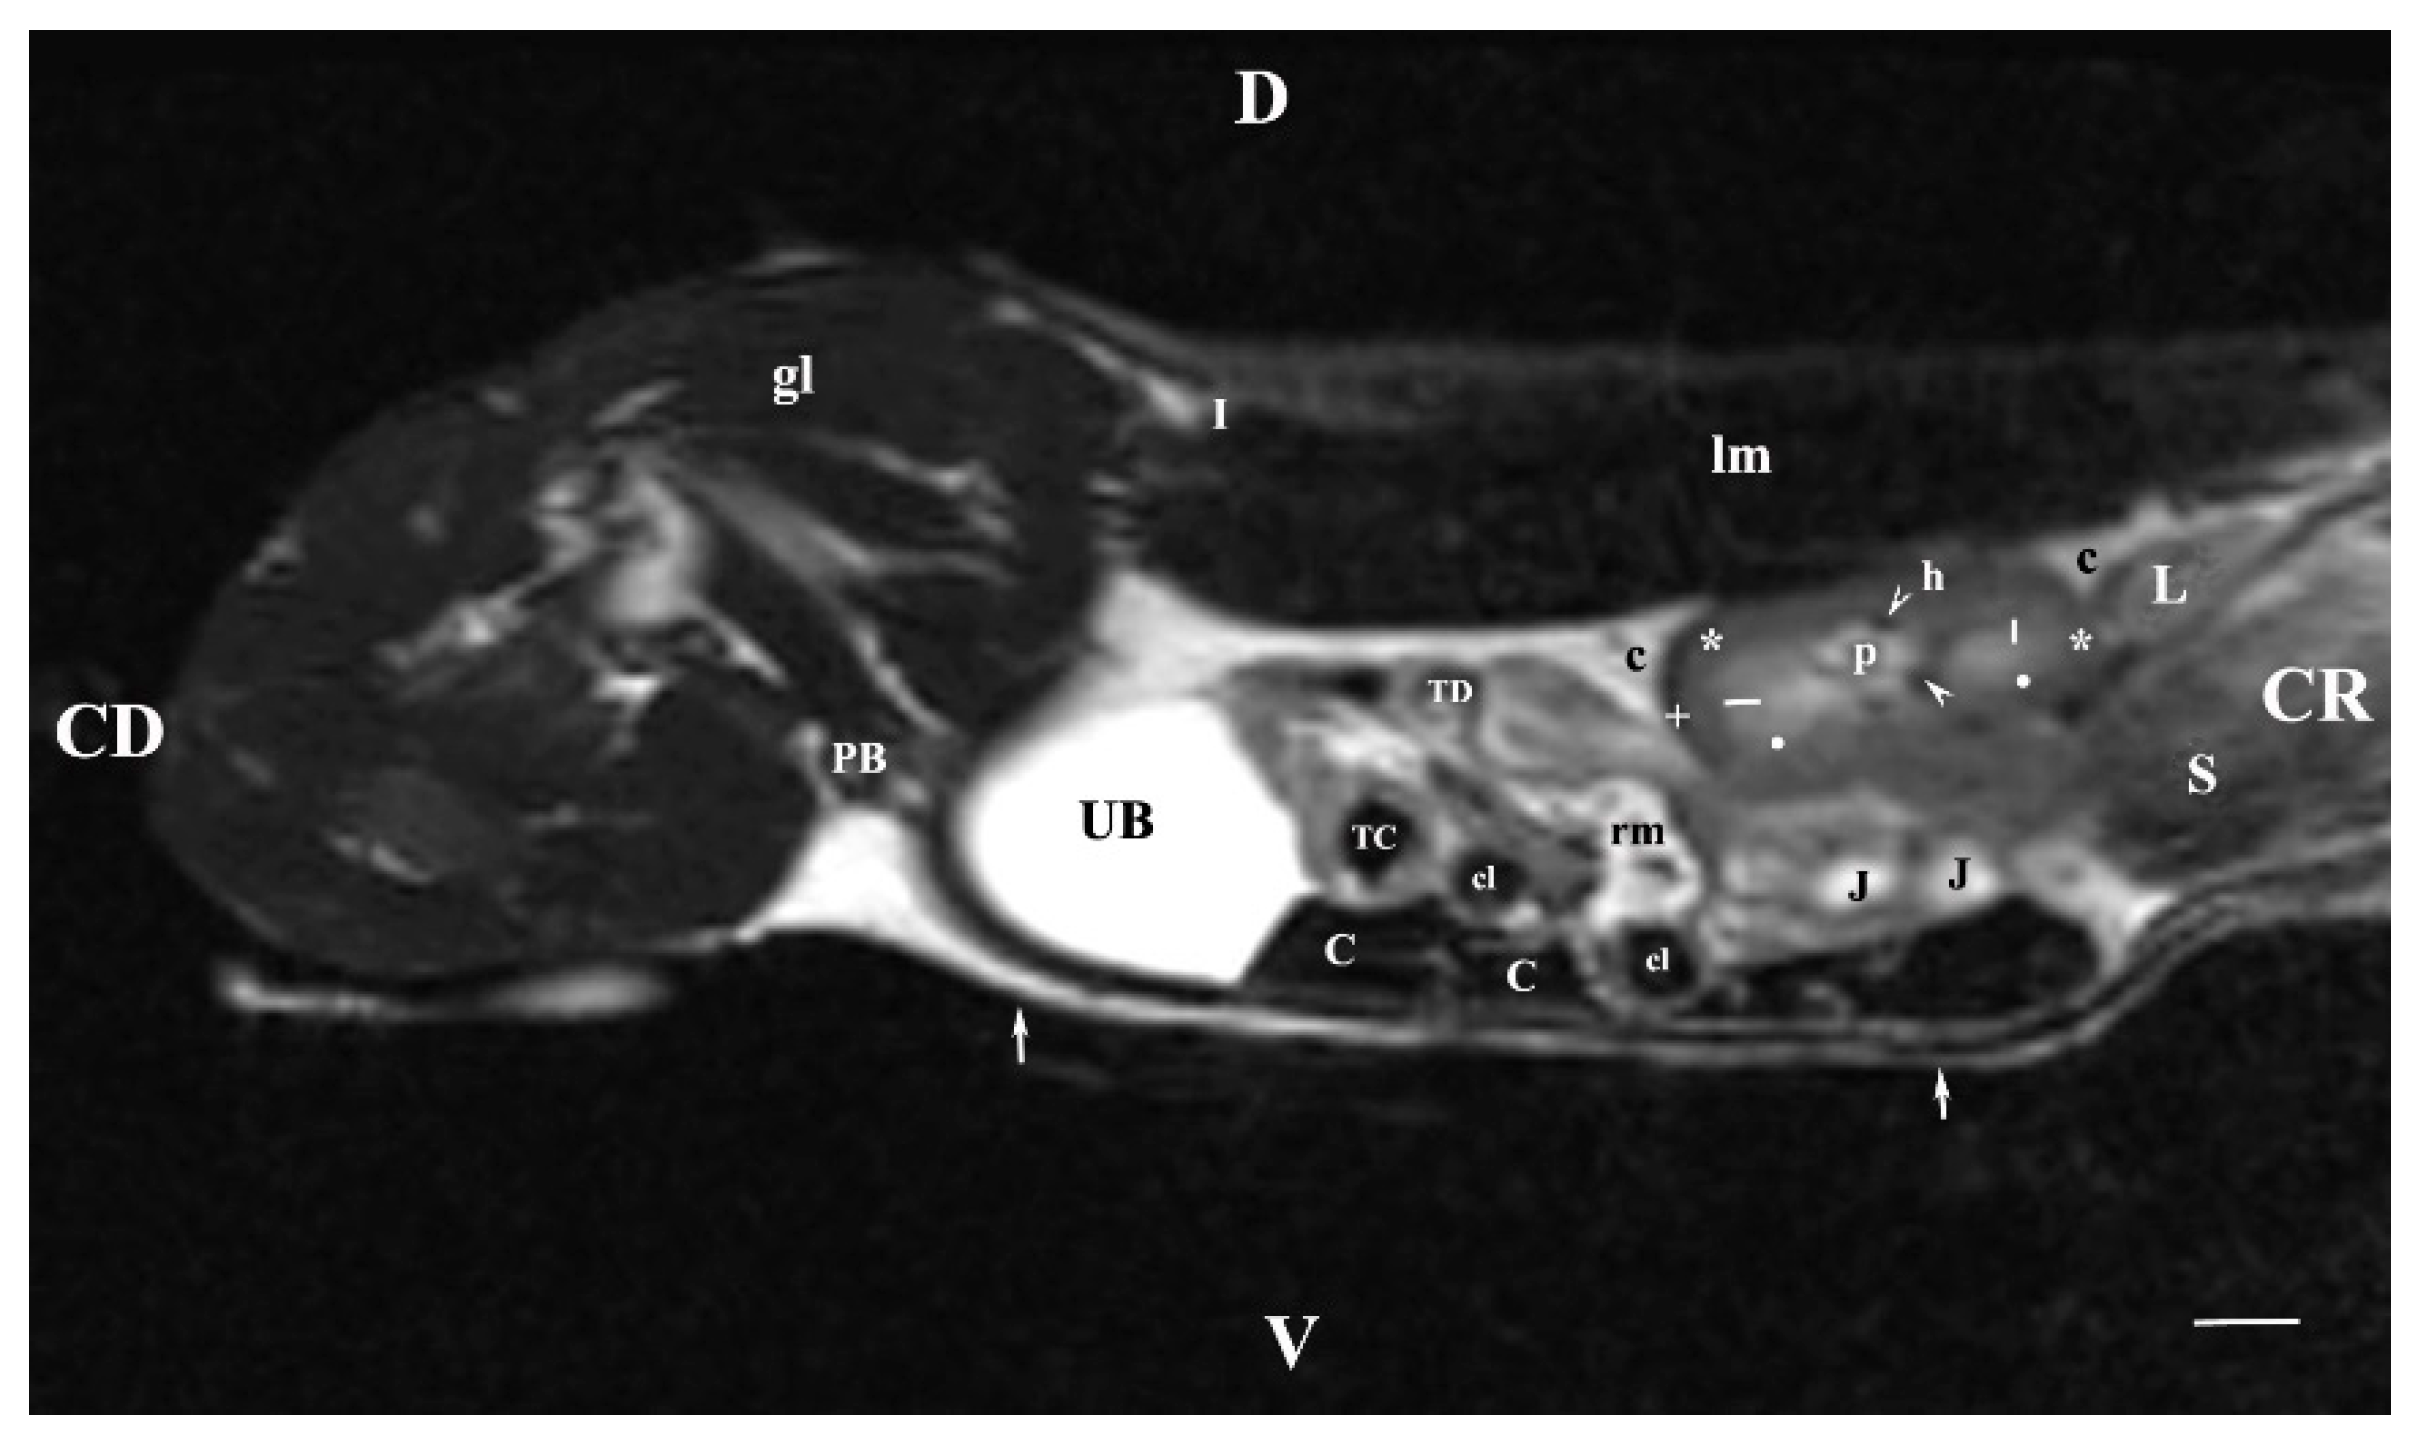

3.1. Transverse MRI